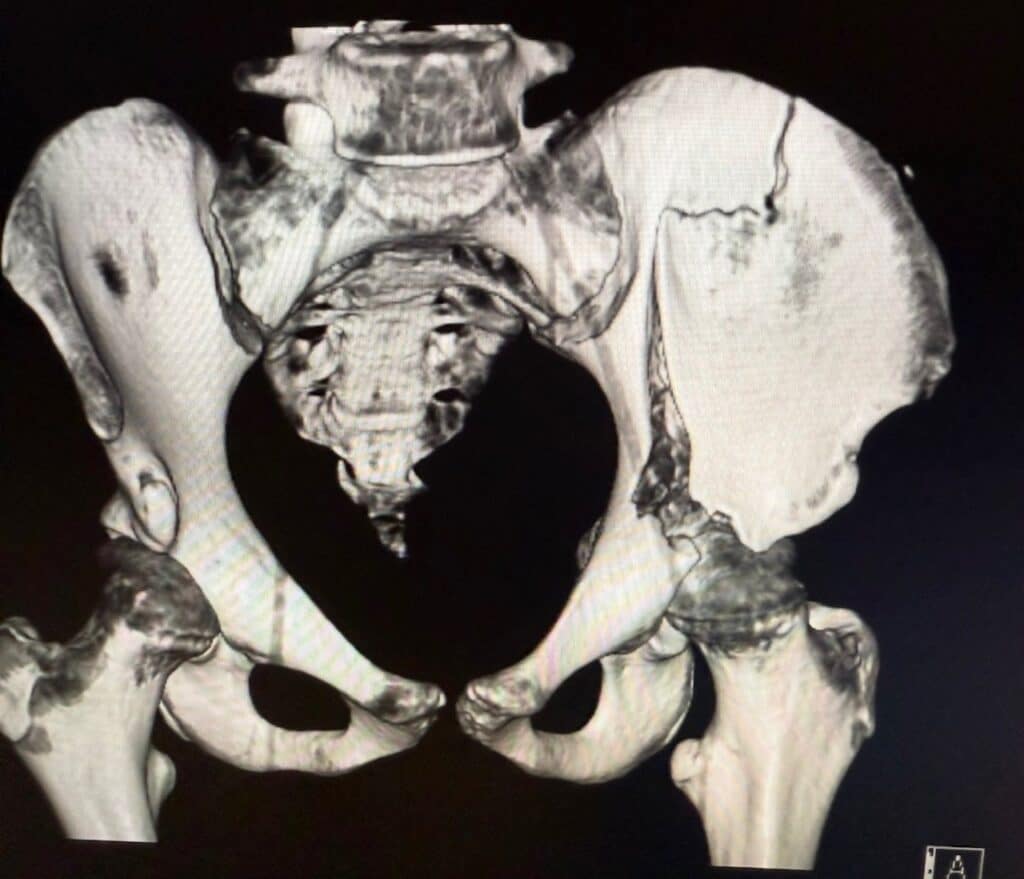

On Saturday 31 May, during a round at Riddell’s Creek, Liv’s season took a dramatic turn. “It was a really unfortunate accident at the show,” she recalls. “My horse’s back legs slipped on the ground coming into the jump, which caused her to fall underneath me. She landed on me and I fully broke my left pelvis in half.”

X-Ray of Olivia’s pelvis following the fall. Image supplied.

“I ended up with

10 screws and two plates

through two large incisions.”

Liv was rushed to the Royal Children’s Hospital in Melbourne, where she faced a long and painful wait for surgery. “I was there for two days waiting for specialist equipment, before undergoing a five-hour operation,” she explains. “I ended up with 10 screws and two plates through two large incisions.”

The severity of the injury meant her Nationals campaign was suddenly in jeopardy. Surgeons initially suggested it could be up to six months before she would return to competition. For a rider used to spending every day in the saddle, the prognosis was tough to hear.